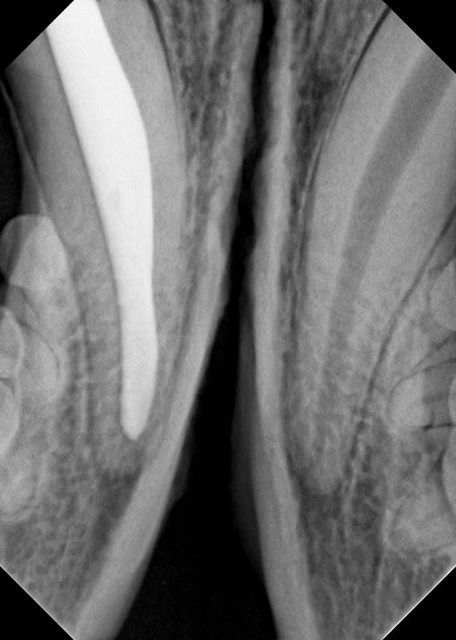

Zuerst wurde die Pulpenhöhle über einen Hilfszugang von vorne eröffnet, um einen  möglichst gradlinigen Zugang zur Wurzelspitze zu erhalten. Dann wurde die eitrig entzündete Pulpa entfernt. Unter Spülung mit desinfizierenden Lösungen wurde die Pulpenhöhle mit dünnen Feilen in aufsteigender Größe gereinigt und ausgeformt. Nach Entfernung der sogenannten Schmierschicht wurde der Pulpenkanal mit Kochsalzlösung gespült und mit feinen Papierspitzen getrocknet. Es schloss sich die Einpassung des sogenannten Master-Points an, eines dünnen Kautschuk-Stiftes aus Guttapercha, der die Wurzelspitze verschließen soll. Hierzu wurde eine kleine Menge  Sealer in die Pulpenhöhle eingebracht, ein Material, das die kleinsten Kanäle im Bereich der Wurzelspitze abdichtet und in Verbindung mit dem Masterpoint den hermetischen Verschluß der Pulpenhöhle Richtung Wurzelspitze übernimmt. Nach dem Einbringen und Verdichten weiterer kleinerer Guttapercha-Stifte erfolgte eine Zwischenfüllung und schließlich eine Deckfüllung aus Kunststoff, um die Pulpenhöhle auch zur Zahnkrone hin abzudichten. Nach Ausarbeitung der Füllung und Politur konnte „Piko“ schließlich aus der Narkose aufwachen. „Piko“ konnte bereits am nächsten Tag wieder arbeiten.